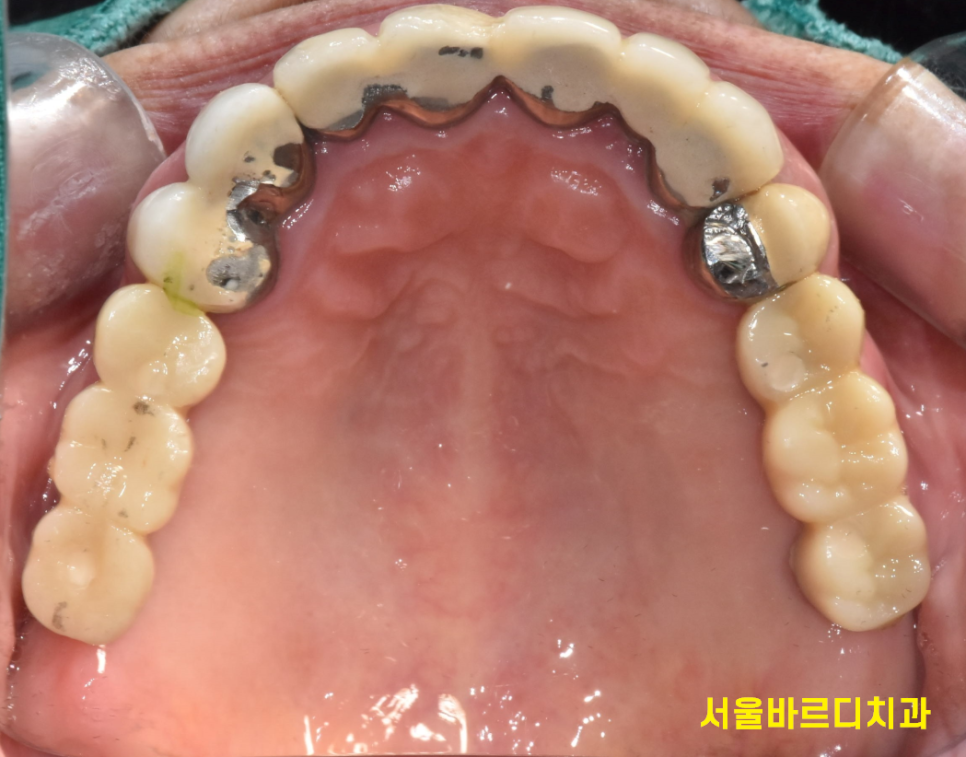

처음 오셨을때 윗니 어금니 6개가 빠져있었는데요.

양쪽 작은 어금니 1개로 식사를 하고 계셨습니다.

230526

오른쪽 위에 어금니는 치아가 없고

아래 어금니의 경우 염증으로 잇몸 뼈가 녹아있었는데요.

문제가 되는 치아와 앞에 치아가 묶여 있어

잘라내서 새로 씌워줘야하고

맨 끝에 치아도 치료 후 보철이 필요하다보니

브릿지로 3개 한번에 씌우는 것을

선택해주셨습니다.